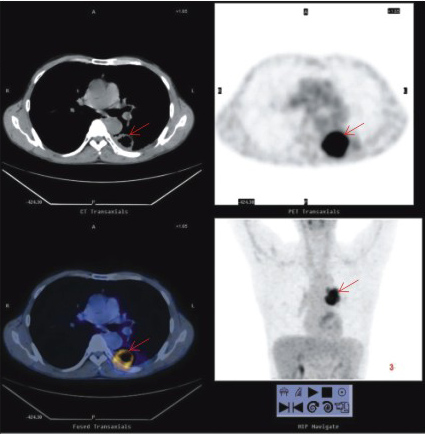

PET-CT一次全身掃描能同時(shí)獲得PET與CT兩者的全身各方位的斷層顯像,它便于病灶的準(zhǔn)確定性和精確定位,便于一目了然了解全身的整體狀況,這對(duì)腫瘤等全身性疾病的診斷、分級(jí)分期和治療方案的制定以及腫瘤原發(fā)病灶的尋找和轉(zhuǎn)移與復(fù)發(fā)的診斷尤為有利。